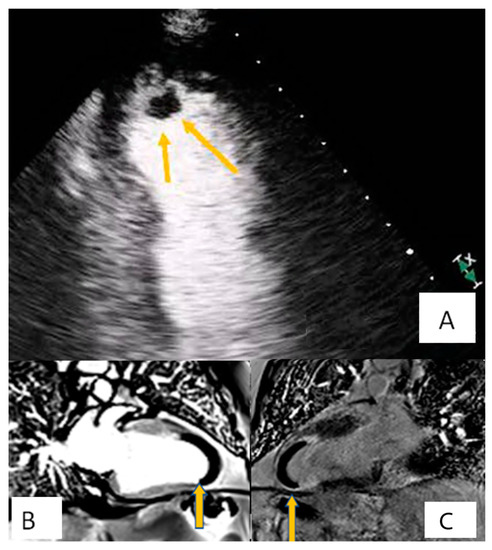

3.1. Transthoracic Echocardiography

3.4. Cardiac Magnetic Resonance

- Tissue characterization on T1–T2 weighted images:

- T1 hypo/isointensity with high T2 weighted signal intensity characterizes the majority of benign or malignant cardiac tumors